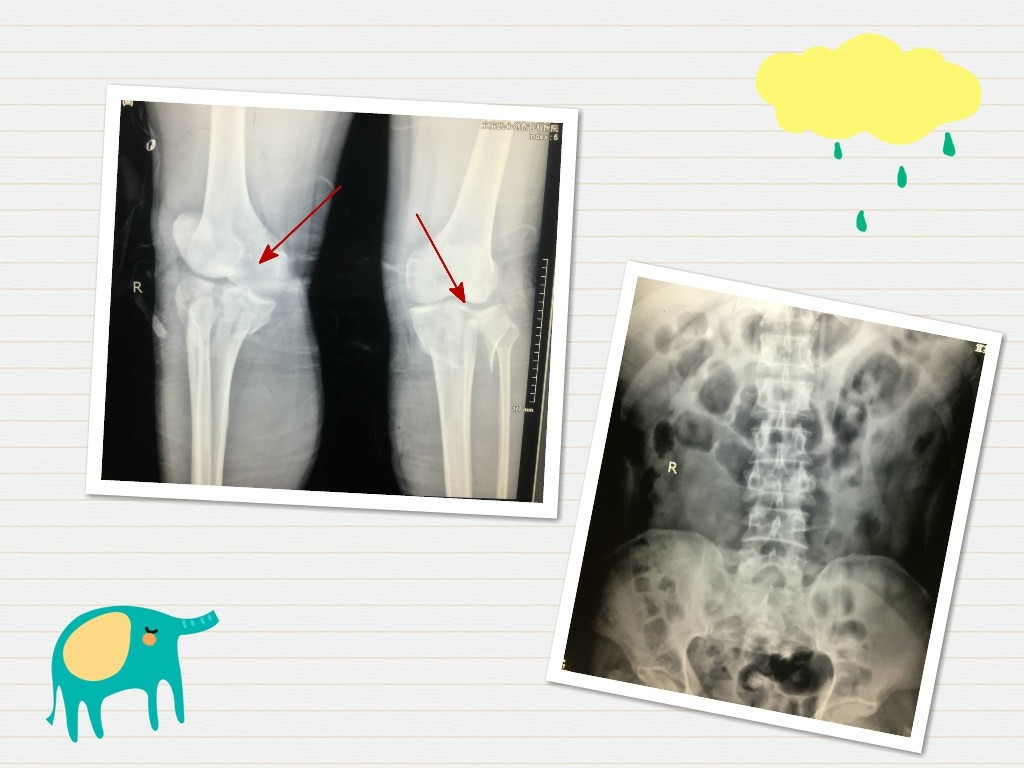

一、全身多处骨折

CT检查结果示:腰3椎爆裂性骨折;右胫骨近端、左胫骨近端粉碎性骨折;左腓骨头骨折;右足舟骨、外楔骨粉碎性骨折;L3椎体左侧椎板骨折、L4椎体后柱线样骨折;L2L3横突骨折;尾椎骨折。

术后6天行二次手术,即左胫骨近端粉碎性骨折切开复位内固定手术,待各项体征稳定后,行第3次手术,即右胫骨近端粉碎性骨折切开复位钢板内固定+植骨术。